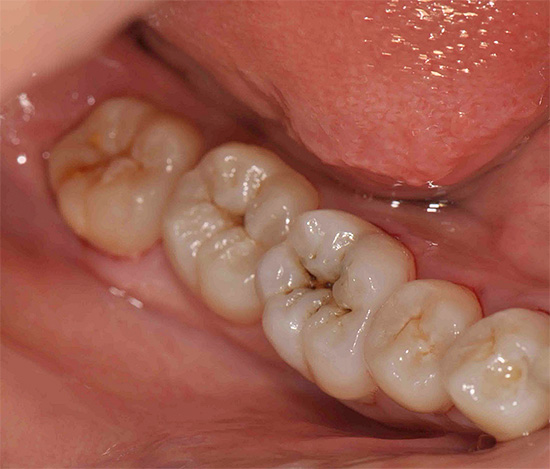

L'ispezione visiva dei denti è il modo principale per identificare una situazione cariogena nella cavità orale. La carie è caratterizzata dal fatto che in quasi tutte le fasi del suo corso, cambia il colore dello smalto dei denti. Anche nella fase spot, quando la dentina non è ancora interessata, lo smalto cessa di essere liscio e lucido e il dentista attento nota facilmente un tale cambiamento.

In fasi successive, determinare la carie con un semplice esame è ancora più semplice: porta alla comparsa di punti neri e marrone scuro sui denti o quando la dentina è danneggiata, sotto lo smalto sono visibili cavità scure.

Non sorprende, nella maggior parte dei casi, la diagnosi visiva della carie dentale può rivelare la maggior parte delle aree interessate. Con lei, il dentista esamina attentamente i denti da diversi lati con uno specchio. Inoltre, il medico può eseguire una sonda sonda: in luoghi dello sviluppo precoce del processo cariato, si avverte chiaramente la rugosità della superficie dello smalto.